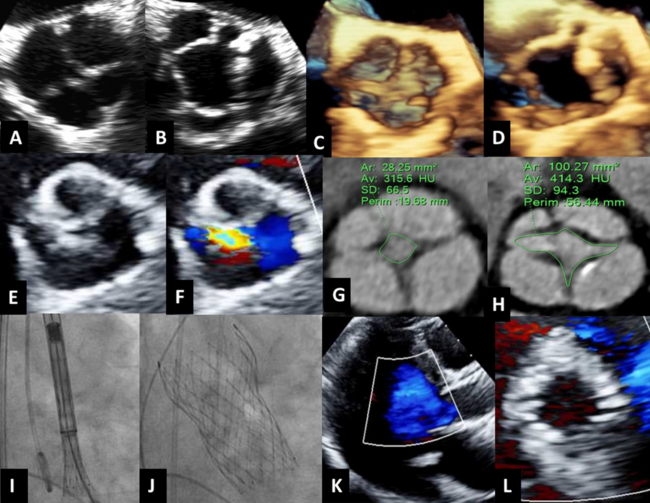

The patient was initially referred for aortic regurgitation where a transesophageal echocardiogram revealed a QAV (Figure A-D) and moderate-to-severe regurgitation. There was no evidence of aortic stenosis at that time. Eight years later, a transthoracic echocardiogram (TTE) was performed due to progressive dyspnea, which showed moderate-to-severe aortic regurgitation and severe aortic stenosis (valve area=1.0 cm² by continuity; Figure E, F). The patient was referred for TAVR given her high surgical risk and frailty. Multidetector computed tomography confirmed severe aortic stenosis and moderate-to-severe aortic regurgitation with a valve area of 1.0 cm² and an effective regurgitant orifice area of 0.28 cm² by planimetry (Figure G, H). The aortic root and access anatomy was favorable for transfemoral TAVR.

The patient underwent a successful TAVR with a 26-mm self-expanding Evolut FX valve (Medtronic) (Figure I, J) and was discharged home the next day. TTE at discharge demonstrated a well-positioned valve with no paravalvular regurgitation (Figure K, L).